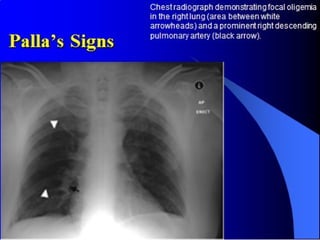

Chest x-ray

• Mostly normal findings

• Done to exclude other pathology

• Pleural effusion/ Atelectatic bands

• Specific signs:

- Hampton’s hump (in infarction)

- Westermark sign

- Palla’s sign

- Fleischner sign (in massive embolism or PHTN)